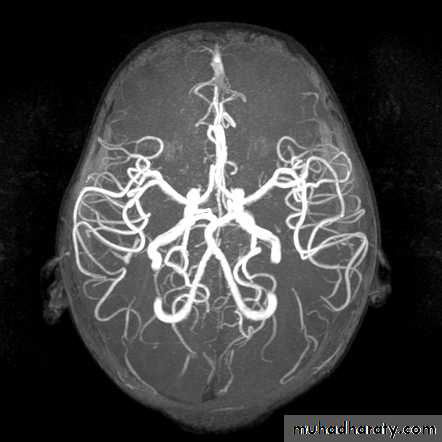

• The cerebral vessels may be imaged non-invasively with MR angiography (MRA).